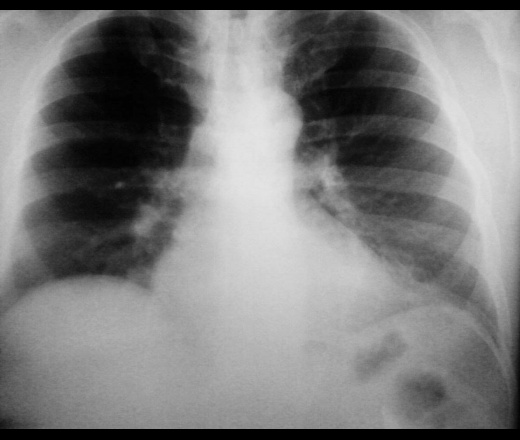

Мужчина 1973 г.р. Гиперстеник. Жалоб не предъявляет. Можно ли расценить затемнение в переднем кардиодиафрагмальном углу слева как абдоминомедиастинальную липому или есть ещё какие-нибудь варианты?( всегда это левый передний кардиодиафрагмальный угол вызывает затруднения!)

Вот снимкм.